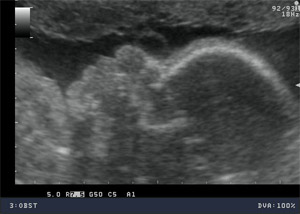

USG prenatalne 18-24 tydzień ciąży

Jest jednym z najważniejszych badań w opiece perinatalnej, polegającym na dokładnej ocenie anatomii i biometrii płodu. Wykonujemy pomiary długości kości udowej – (Femur length - FL); wymiaru dwuciemieniowego główki płodu (Biparietal diameter - BPD); obwodu główki płodu (Head circumference – HC) oraz obwodu brzuszka płodu (abdominal circumference - AC). Na podstawie tych parametrów możemy ocenić prawidłowe wzrastanie oraz masę płodu.

Jest to okres najlepszej dostępności dla oceny struktur płodu w czasie życia wewnątrzmacicznego.

W czasie badania ultrasonograficznego możemy szczegółowo ocenić struktury ośrodkowego układu nerwowego, układu moczowego, pokarmowego, kostnego, a także serca, kończyn, twarzoczaszki, łożyska i płynu owodniowego.